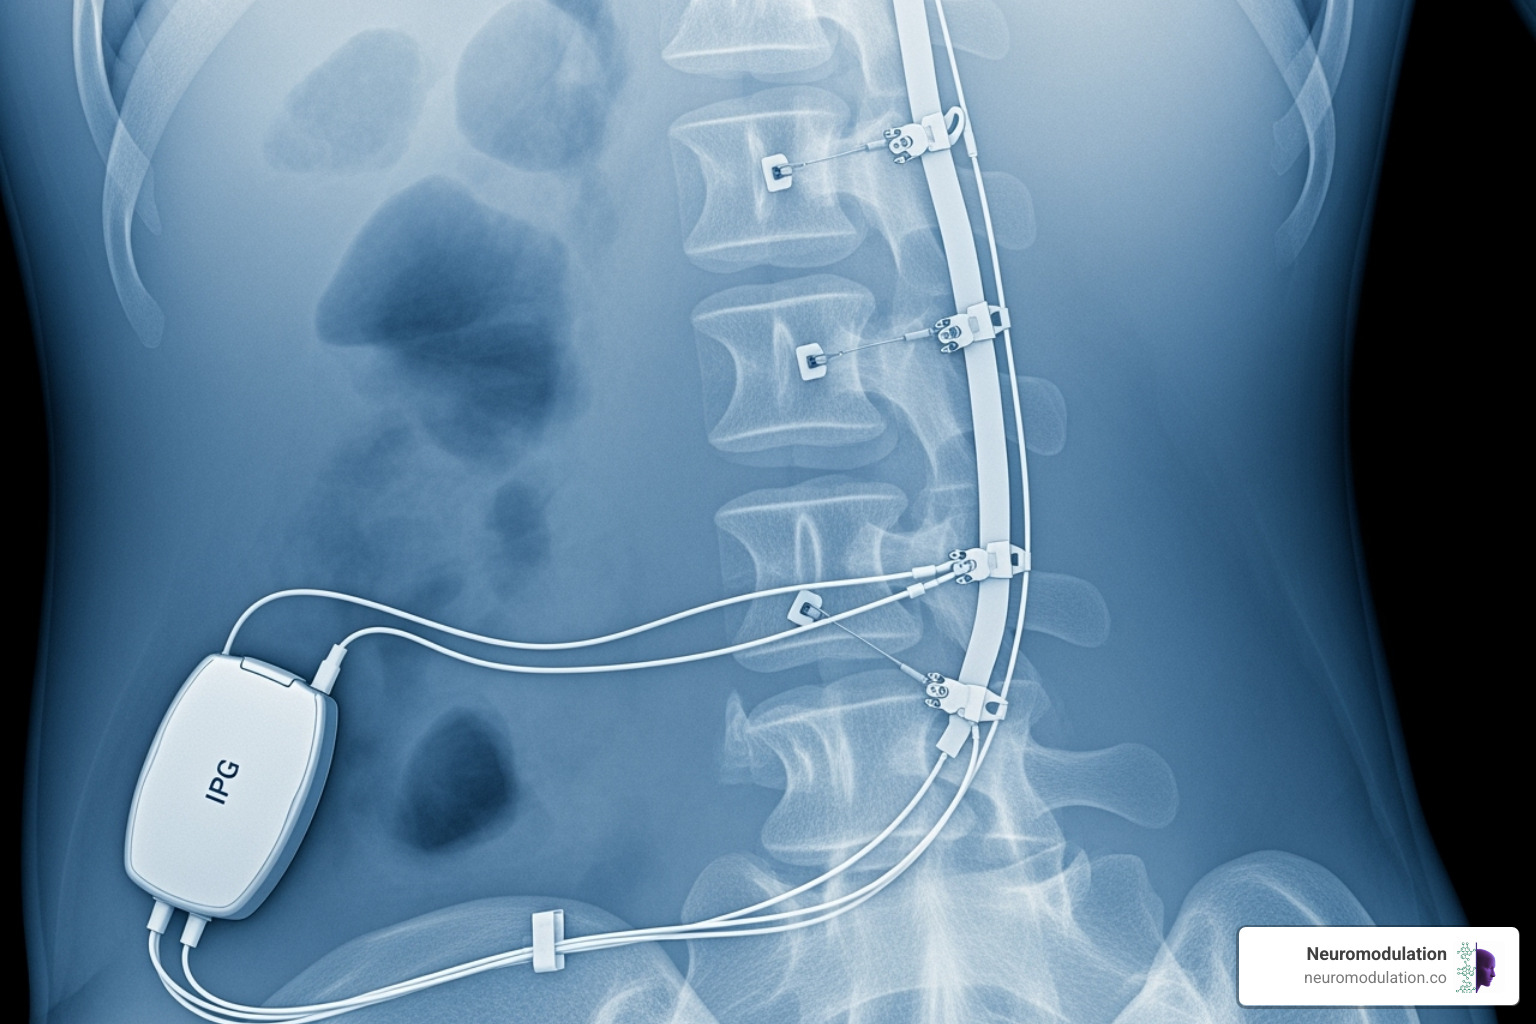

Device and Stimulation-Related Side Effects

Once the SCS device is implanted, complications related to the hardware or the electrical stimulation can occur. These SCS side effects require awareness of what to watch for and when to contact your medical team.

Lead migration is a top concern. The leads, which deliver electrical impulses, can shift from their precise placement. When this happens, stimulation may affect unintended areas or pain relief may diminish as the electrical field misses its target.

Lead breakage is another mechanical challenge. The delicate wires can fracture over time due to the stress of daily movement, interrupting the electrical pathway and reducing effectiveness.

Battery failure is inevitable. When the battery in the internal pulse generator weakens, you will notice changes in stimulation, requiring a surgical procedure for replacement.

The stimulation itself can cause unpleasant sensations. Instead of a gentle tingling, some patients find the sensation bothersome or experience jolting or shocking sensations. If leads are not positioned correctly, you might feel stimulation in completely wrong areas, creating new discomfort.

Hardware issues are the most common reason for revision surgery after SCS implantation.

- Lead migration affects most patients to some degree. Research shows 88.5% of leads migrate within 20 days, but only 1.1% of patients require revision surgery due to loss of efficacy. Migration can cause stimulation in unintended areas or a drop in pain relief. Scientific research on lead migration provides more detail.

- Lead fracture occurs when wires break from mechanical stress, interrupting therapy.

- Battery depletion is predictable. Primary-cell batteries last about 3.7 years, while rechargeable systems last around 7.2 years, eventually requiring replacement.

- The need for revision surgery stems mainly from lead migration, breakage, or routine battery replacement.